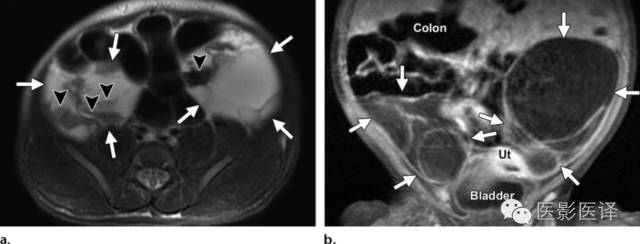

图5.双侧出血性新生儿卵巢囊肿。新生儿MR图像用于评估在外院胎儿超声中发现的两个实性腹内占位。(a)轴位脂肪饱和T2WI MR图像显示双侧多房的附件占位(a和b箭),伴有液液平面(箭头),提示出血。(b)冠状位脂肪饱和T1WI增强MR成像显示双侧占位无实性成分(箭)。多囊占位独立于结肠、肝脏、脾脏和肾脏,在膀胱上方。双侧病变均位于中线外侧。强化的子宫(Ut)在膀胱上方。